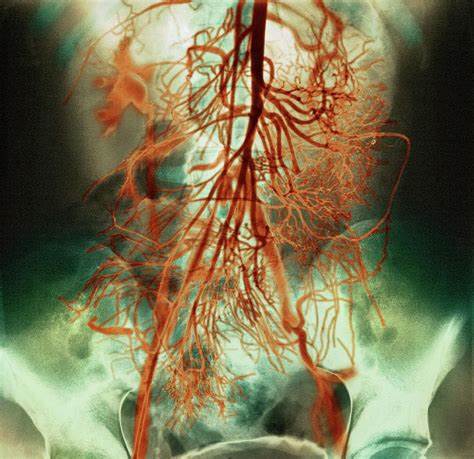

20. Your arteries may unclog

Image source/Fine Art AmericaClogged arteries in the body mean that the blood cannot flow properly which can lead to many different illnesses or diseases. But a vegan diet may perhaps help to slowly unclog your arteries meaning that the blood flow through the arteries may improve.

27. It may increase blood flow

Image source/about.comVeganism may in fact improve the blood flow throughout your body. It has been suggested by certain sourced that there is apparently an agent in meat that thickens blood and therefore can make blood flower slower or harder over time - so it may help to cut out meat.